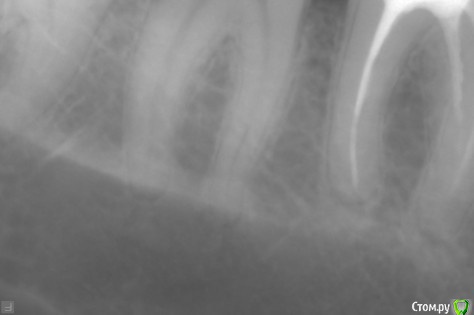

Иван_maa Опубликовано 30 октября, 2015 Поделиться Опубликовано 30 октября, 2015 В начале месяца зафиксировал кариес коренного зуба.Сегодня сходил на консультацию, сделал снимок, сказали, сто пульпит. Есть вероятность, что не будет, но очень малая. Есть клиники и врачи, которые могут вылечить без пульпита в Москве и Подмосковье ? За умеренную цену. фото прилагается. Ссылка на комментарий

Ker Опубликовано 27 ноября, 2015 Поделиться Опубликовано 27 ноября, 2015 Пульпит там, и еще полость средняя на дисталке. Ссылка на комментарий